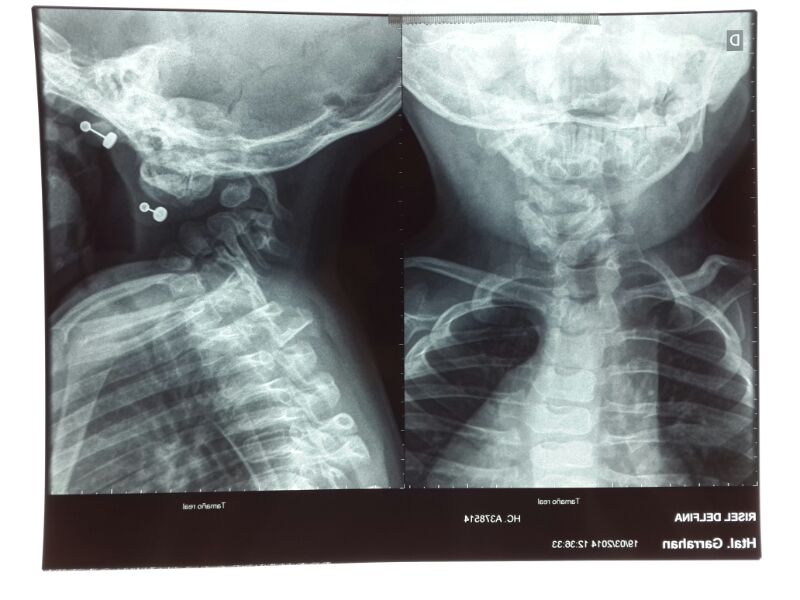

- Figura 8. Radiografías cervical AP y Lateral